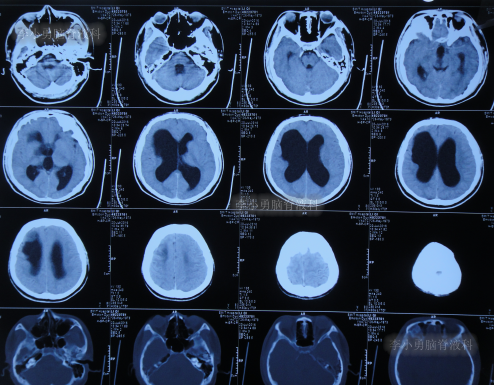

发现脑积水11年即2016年7月20日,复查头颅CT(图-2)后,仍建议继续定期观察。

图-2:2016年7月20日头颅CT